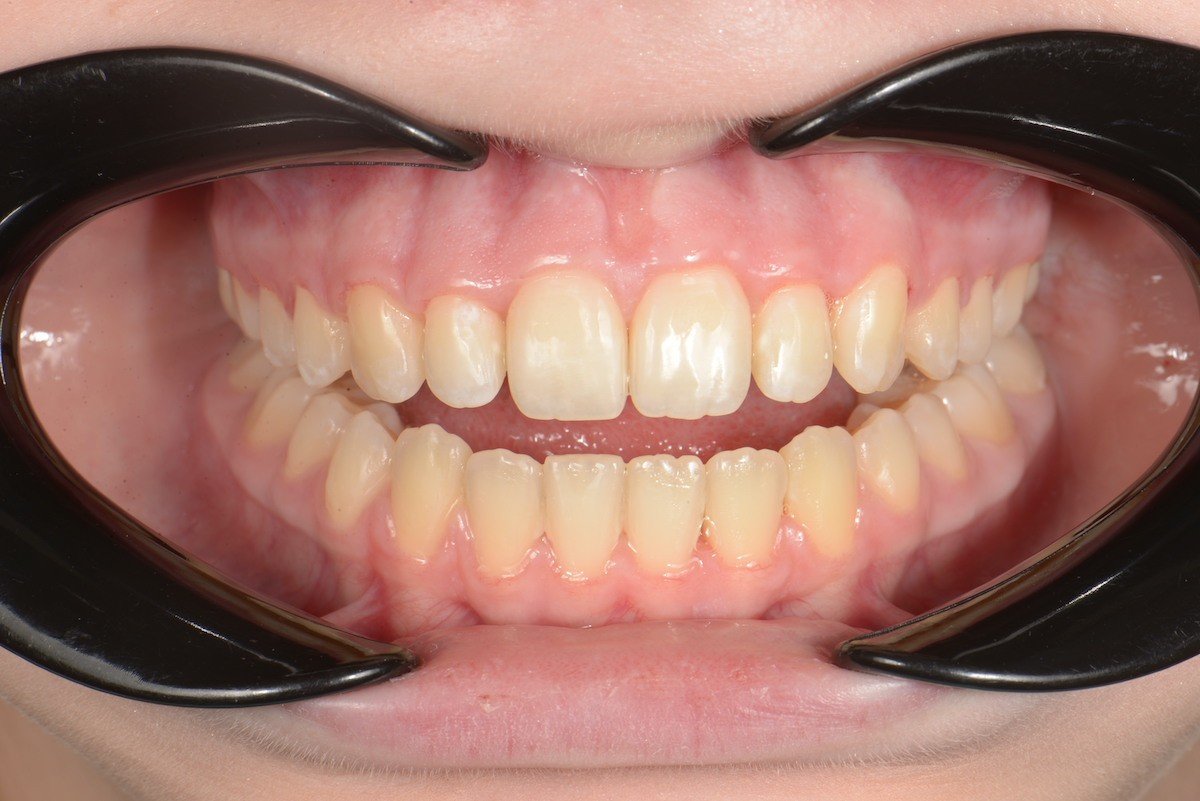

Get the bright white smile you’ve always wanted! Contact us today to get your $139 whitening trays.